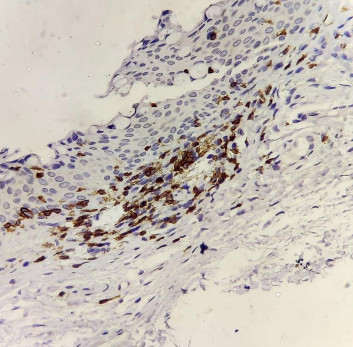

CD68+ cells stained brown (magnification 40X) on immunohistochemistry.